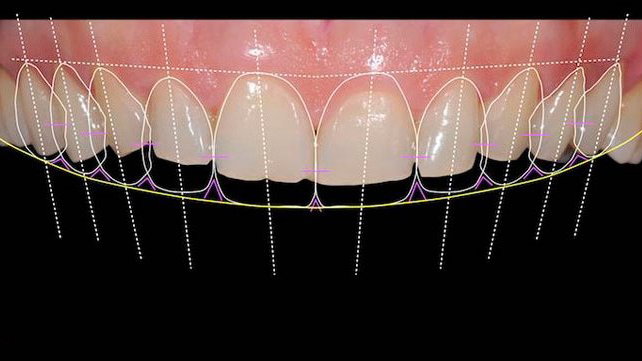

Digital Smile Designing

Digital smile design is a digital treatment planning tool that enhances diagnostic vision and improves predictability which helps to create beautiful smiles. With this we can plan treatment more effectively as a team, and perform better treatments in a more efficient way.